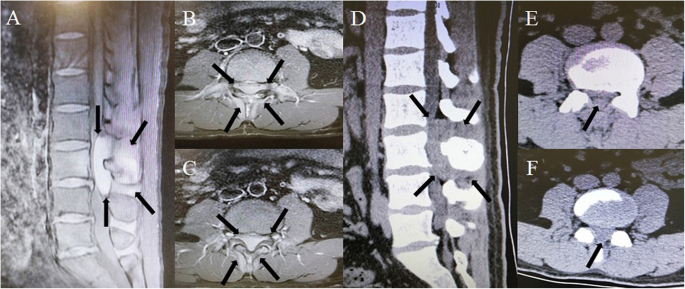

Diagnostic imaging: Lumbar enhanced magnetic resonance imaging (MRI) revealed a lumbar canal iso-intense lesion at L2 to L4 and a compressed spinal cord (Fig. 1a, b, c). A computed tomography (CT) scan of the spine showed an iso-dense, fusiform, soft lesion, and slight bone destruction at L2 to L4 (Fig. 1d, e, f). A whole body bone scan with single photon emission computed tomography (SPECT) demonstrated abnormal 99mTc- methylene diphosphonate (MDP) accumulation in the L3 lamina and spinous process on fused SPECT/CT. No other signs of bone destruction or metastasis were found in the SPECT images (Fig. 2). However, as the exact character of the lesion was not clear from the images of the tumor, hematoma and abscess were not ruled out.

Preoperative enhanced T1-weighted magnetic resonance images (MRI) of the lumbar spine. a Sagittal and (b) (c) transverse views show an iso-intense, fusiform, high-signal lesion in the L2 to L4 vertebral canal, with complete compression of the local spinal cord and a mixed signal around the L3 lamina, spinous process, and soft tissue. Preoperative computed tomography (CT) of the lumbar spine. d Sagittal and (e) (f) transverse views show an iso-dense fusiform soft lesion at the L2 to L4 lumbar canal with local spinal cord compression and slight bone destruction.The black arrows show the scope of the lesion